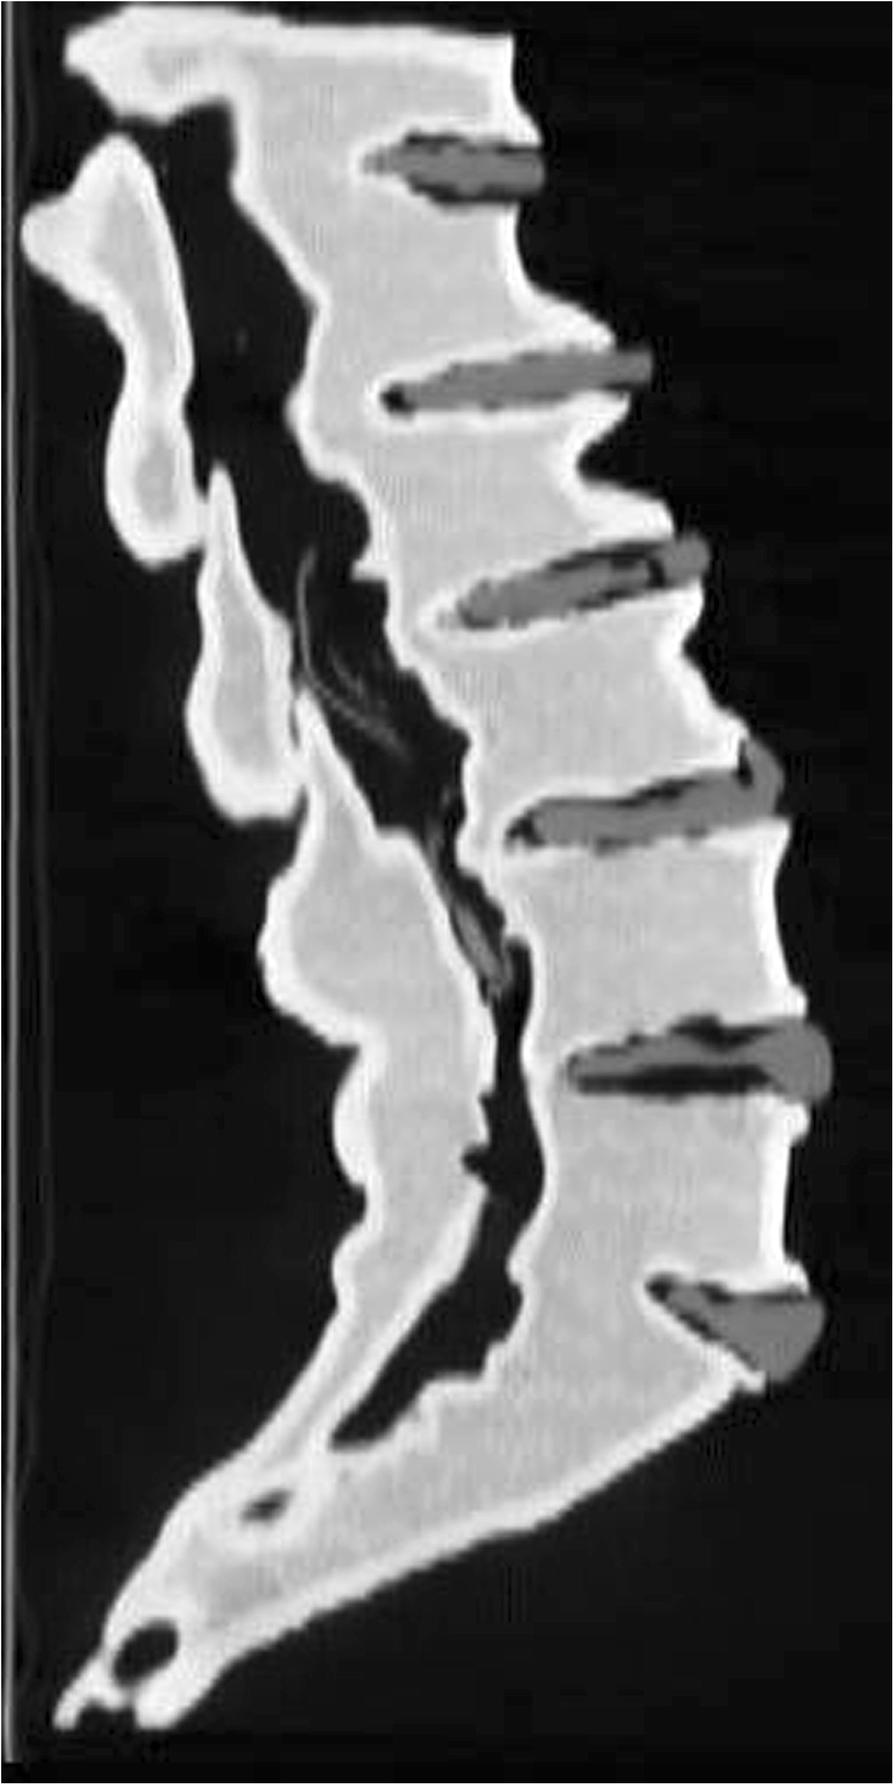

Sagittal reformat of CT of the lumbar spine model, demonstrating differential densities and ability to distinguish the vertebral bodies, discs and nerve roots